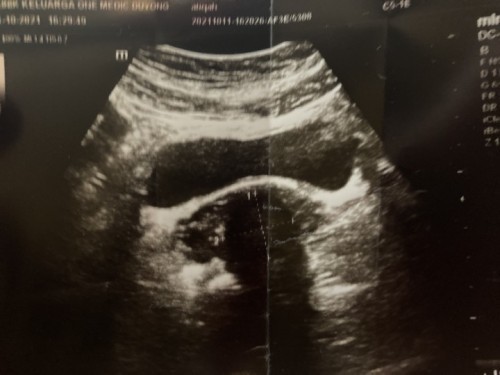

Hai semua saya nak tnya semua sy dh buat upt and semakin terang tp malangnya dr scan and suspect mcm fibroid di rahim cume dr x pasti sama ada dlm rahim or luar rahim..tp kalau ikut saiz dr msih kcil…sminggu sblm tu sy de buat scan skli lg,dgn dr lain and dr tu kata rahim tebal and ada cyst..jdik sy kliru skrg ni..dan stress juga pkirkan..ada ssiapa blh bntu? Atau yg pnah mgalami situasi mcm sy.. Terima kasih